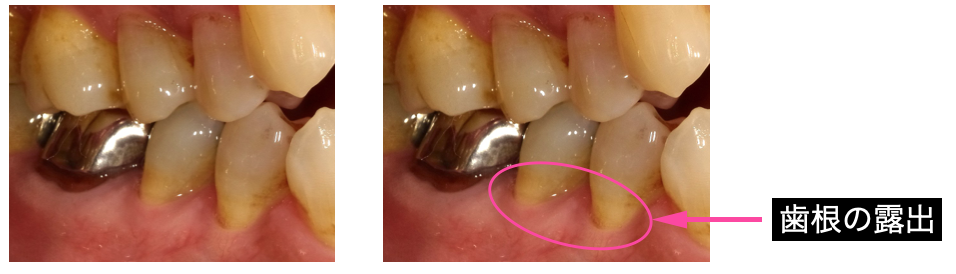

②歯茎が下がって歯根が露出している。

歯周病や過度な圧力でのブラッシングなどによって歯根が露出することもしみる原因になります。

歯周病治療やブラッシングのアドバイスによりしみが改善することもあります。